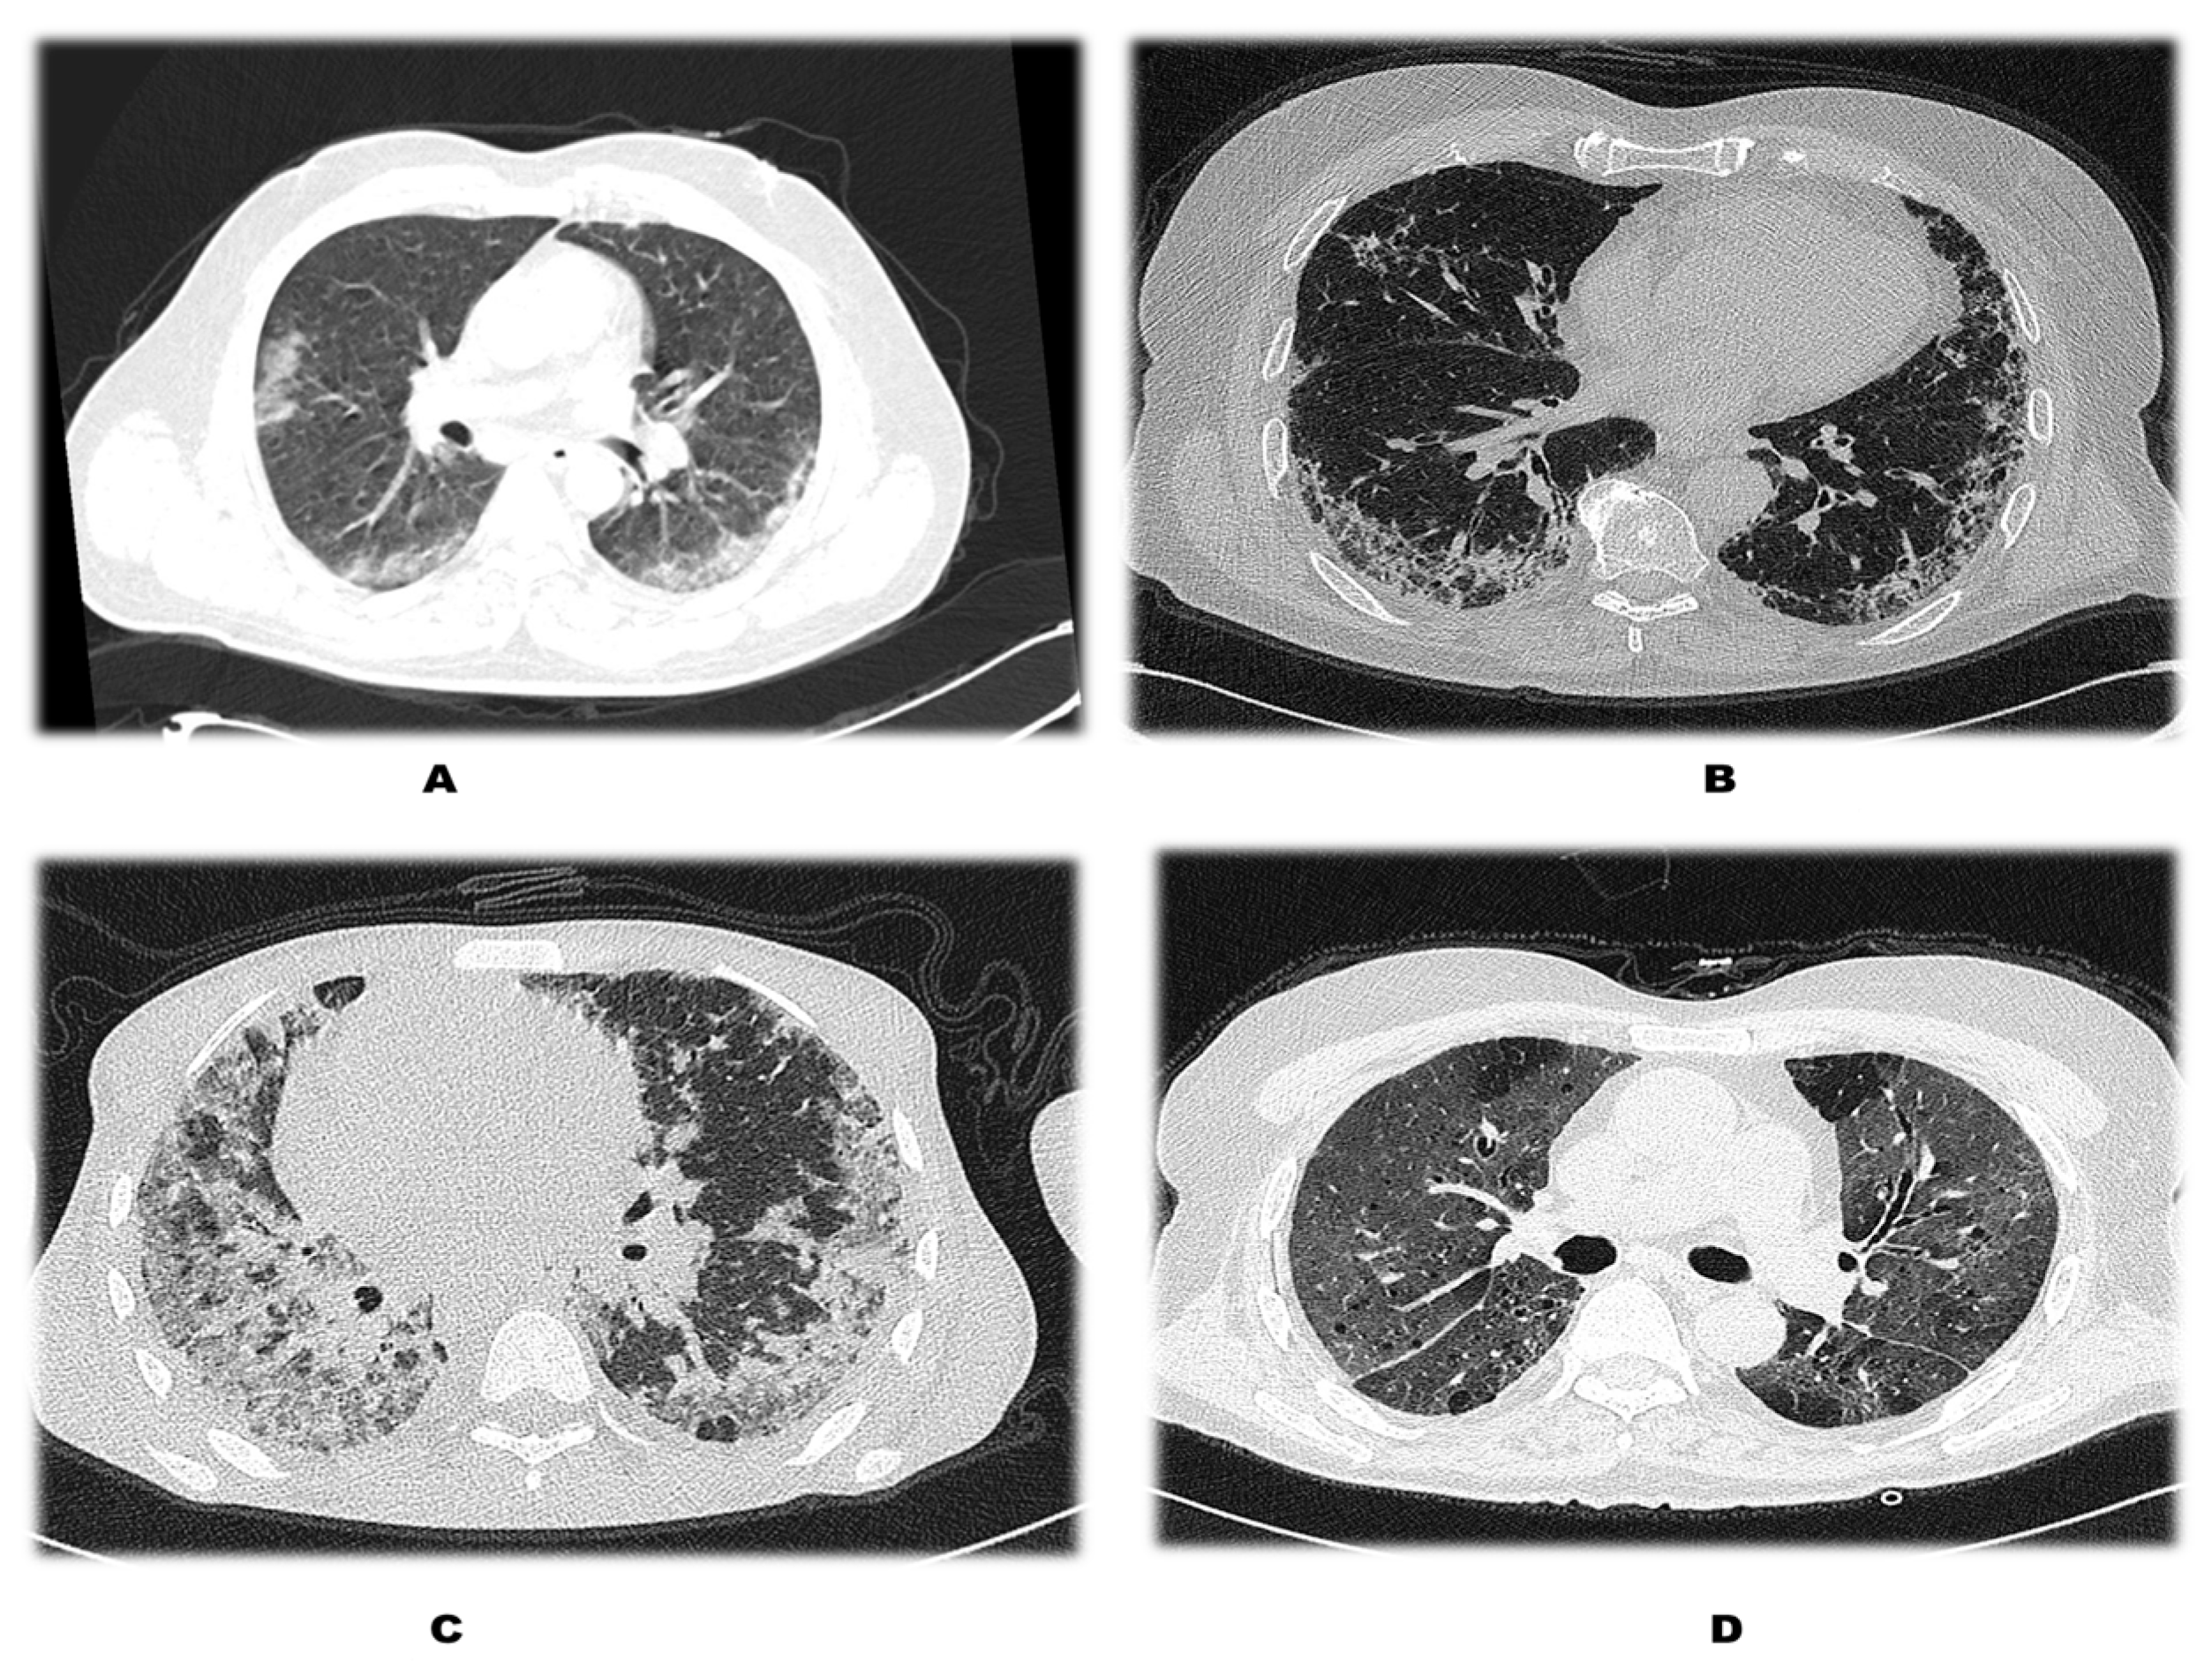

| CT Severity Score | Patients without DM (n = 115) | Patients with DM (n = 37) | Total | p Value |

| 0–11 {Mild} | 65 (56.52%) | 12 (32.43%) | 77 (50.66%) | 0.024 |

| 12–18 {Moderate} | 46 (40%) | 22 (59.46%) | 68 (44.74%) | |

| >18 {Severe} | 4 (3.48%) | 3 (8.11%) | 7 (4.61%) | |

| Total | 115 (100%) | 37 (100%) | 152 (100%) |